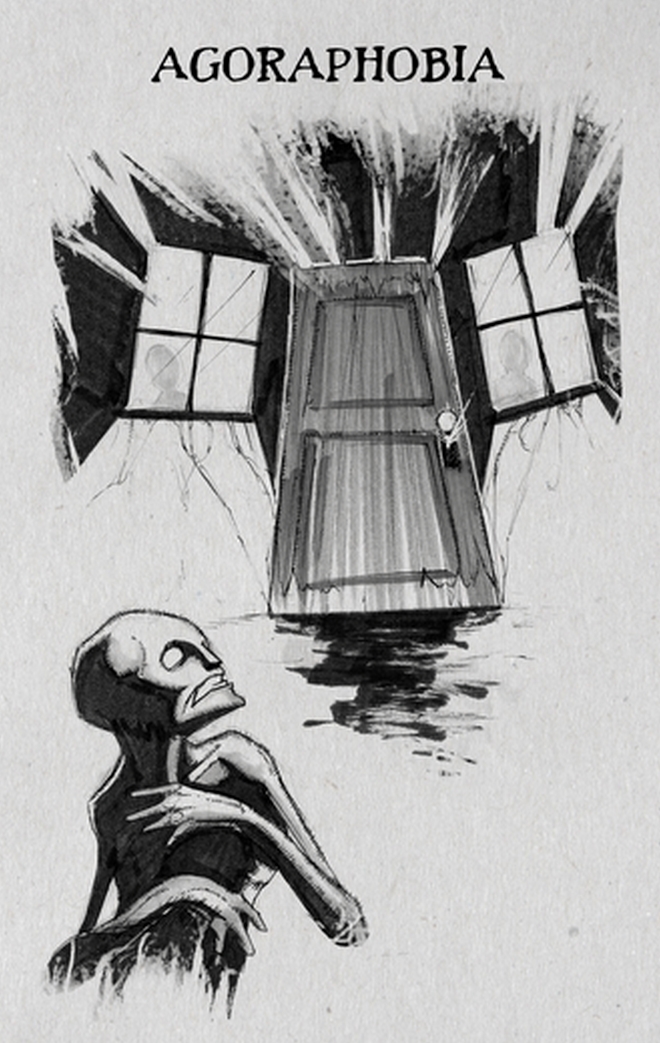

Αγοραφοβία